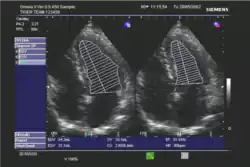

Die Ejektionsfraktion kann mit verschiedenen Untersuchungsverfahren gemessen werden, in absteigender Häufigkeit:

- Echokardiographie

In der klinischen Praxis erfolgt die Abschätzung der Ejektionsfraktion häufig nach dem visuellen Eindruck; dies wird bei subjektiv normaler Pumpfunktion als ausreichend angesehen. Bei eingeschränkter Pumpfunktion sollte eine quantitative Bestimmung mit Hilfe der Scheibchensummationsmethode nach Simpson erfolgen;[3] die Quantifizierung mittels M-Mode nach Teichholz wird als zu ungenau angesehen.[3][4]